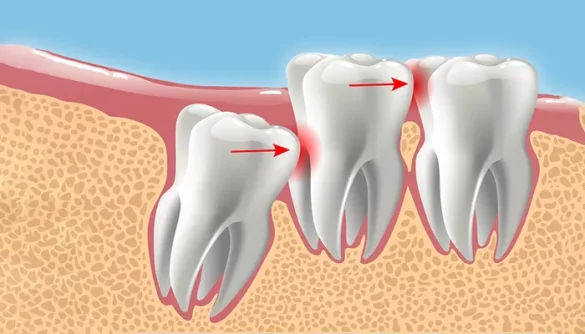

The eruption of wisdom teeth generally occurs between the ages of 17 and 25. However, in some individuals, wisdom teeth may not erupt at all. Instead, they may remain impacted within the jawbone or gums. This delayed or absent eruption can lead to complications such as gum inflammation, cyst formation, or gum disease.

When there is not enough space in the jaw, wisdom teeth may become impacted. This means they remain trapped beneath the gum or grow at an angle. Impacted teeth can lead to intense pain, infection, cysts, and even damage to neighboring teeth.